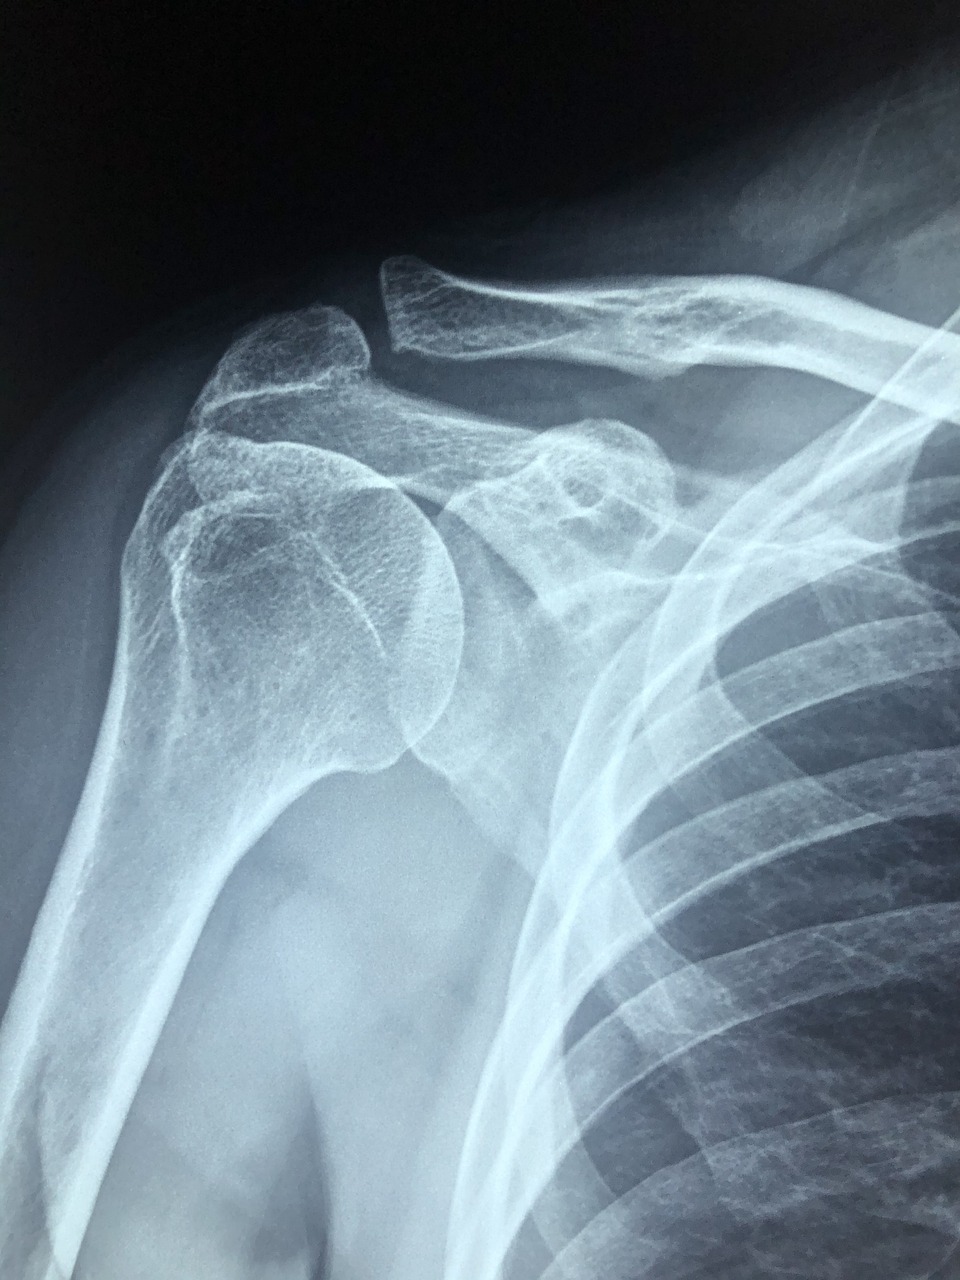

극상건에 발생하는 석회에 경우에는 X-ray 검사로 쉽게 발견이 가능하며, 석회가 관찰될 경우 석회성 건염으로 진단하여 치료를 하게 된다. 하지만 다른 회전근개(견갑하건, 극하건, 소원건)에 발생한 석회는 단순 X-ray 검사로 보이지 않은 경우가 있다. 이러한 경우 MRI, 초음파 등으로 검사를 진행한다.

석회성건염은 단독으로 발생하는 경우도 있지만 회전근개파열과 동반하는 경우도 있기 때문에 이러한 다른 어깨 질환을 정확히 확인을 하기 위해 MRI 검사가 필요하기도 한다.